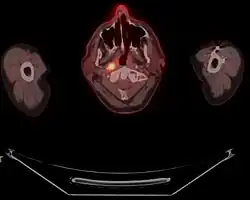

Carcinome du nasopharynx

Le carcinome du nasopharynx est un cancer se développant à partir des cellules épithéliales du nasopharynx. Il fait partie des cancers des voies aérodigestives supérieures. Il s'agit du cancer épithélial le plus fréquent chez l'adulte.

Cette tumeur peut rester localisée ou s'étendre vers la base du crâne, l'oropharynx, la cavité buccale et le palais. Les métastases sont typiquement des métastases ganglionnaires cervicales. Ces métastases sont souvent le mode de diagnostic de ce cancer. La biopsie donnant le diagnostic. Les autres signes comprennent douleur, trismus, otite, régurgitation nasale par parésie nerveuse, perte de l'audition et paralysie de nerfs crâniens.

Les métastases ganglionnaires sont souvent le mode de révélation de ce cancer. La biopsie donnant le diagnostic. Les autres signes comprennent douleur, trismus, otite, régurgitation nasale par parésie nerveuse, perte de l'audition et paralysie de nerfs crâniens.

Diagnostic

La biopsie fait le diagnostic. Une évaluation de l'extension est indispensable permettant une prise en charge optimale[7],[8].